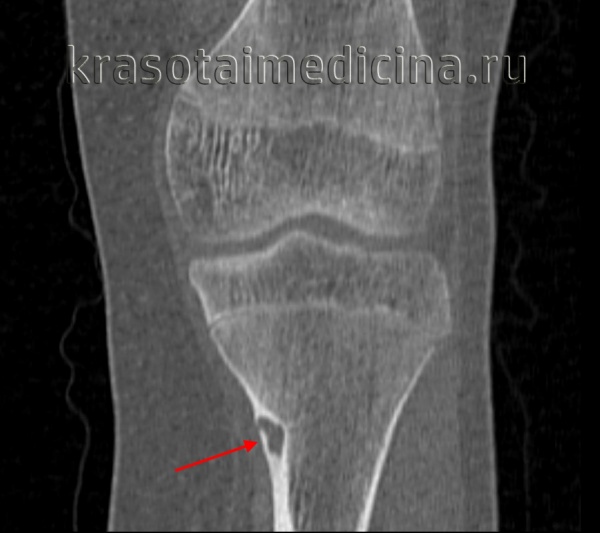

Рентгенограмма остеоид-остеомы проксимального отдела бедра. Имеется рентген-прозрачное образование с четкими контурами, окруженное склерозированной костью. Размеры прозрачного участка всегда меньше 1,5 см. Рентгенограмма голени в прямой проекции: остеоид-остеома малоберцовой кости. Обратите внимание на доброкачественный характер реакции кортикального слоя и увеличение объема кости. Остеоид-остеома диафиза бедра. Обратите внимание на утолщение кортикального слоя кости и доброкачественное периостальное новообразование костной ткани. Еще одним характерным признаком заболевания является интрамедуллярный склероз (стрелка). После рентгенографии методом выбора для диагностики остеоид-остеом является КТ, — очень чувствительный метод обнаружения при интра- и юкстакортикальном расположении «гнезда». Такое поражение сопровождается значительным утолщением кортикального слоя. Обратите внимание на случайное близкое расположение питающей артерии. Очень чувствительным методом диагностики остеоид-остеом является сцинтиграфия костей. В данном случае отмечается значительное усиление сигнала от пораженных дистальных отделов бедренных костей. Аксиальный КТ-срез (а) и взвешенный по Т2 МР-скан (б) с типичными признаками юкстакортикальной остеоид-остеомы дистального отдела бедра. На КТ виден типичный медуллярный склероз вокруг образования. На МРТ—выраженный сопутствующий отек костного мозга и периостальная реакция прилежащей надкостницы. Отечность проксимальной фаланги указательного пальца вследствие остеоид-остеомы. Интраоперационная картина «гнезда». Макропрепарат. «Гнездо» обычно имеет вишневокрасную окраску. При микроскопическом исследовании видны тонкие, хаотично расположенные остеоидные трабекулы, между трабекулами располагается богатая сосудами рыхлая соединительная ткань. При большем увеличении в веществе остеоида видны одинакового вида остеобласты без атипии ядер.

(Слева) Рентгенография в боковой проекции: кортикально-диафизарная ОО с выраженным утолщением заднего кортикального слоя большеберцовой кости. Утолщенная кость скрывает собственно гнездо опухоли

(Справа) КТ, аксиальная проекция, без контрастного усиления: у этого же пациента визуализируется задняя периостальная реакция в виде нагромождения, окружающая округлый литический очаг, глубоко погруженный в кортикальный слой. Эта ОО располагается непосредственно около питающего сосуда. Такое взаимоотношение наблюдается часто. (Слева) Рентгенография в боковой проекции: овальный литический очаг и окружающая его зона склероза В, которые позволяют диагностировать ОО.